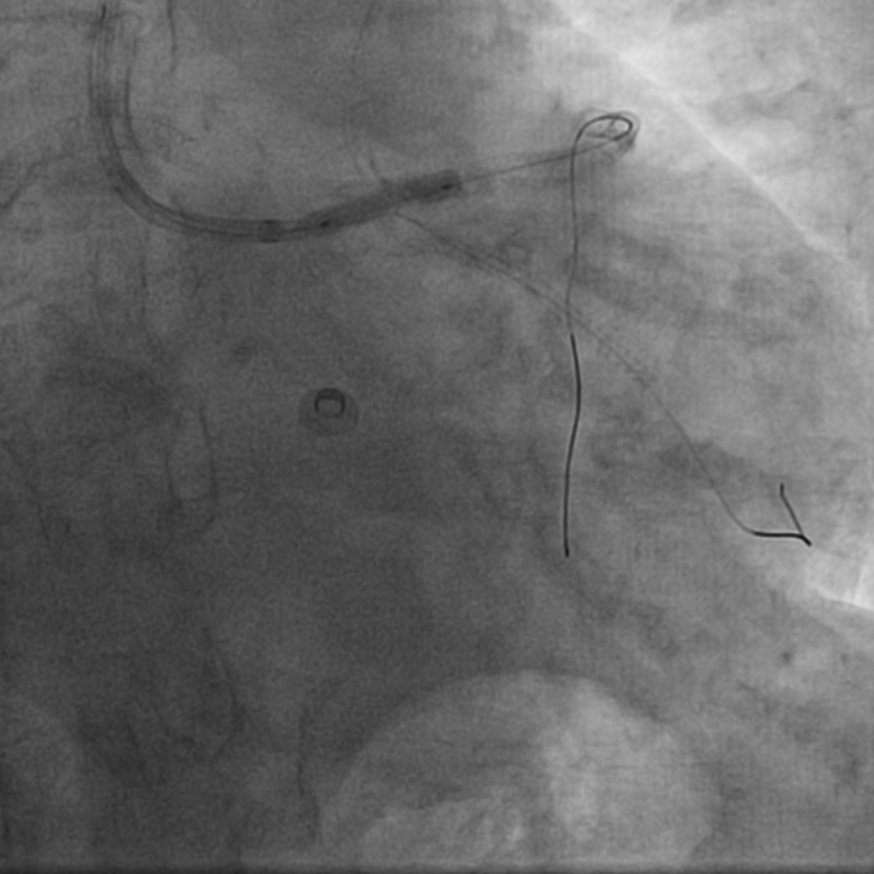

图1 外院手术过程,RCA无法扩张

该患者为68岁女性,14年前于当地医院接受冠脉介入治疗,于左主干至前降支、回旋支及右冠状动脉共植入5枚支架,近10天来再次出现劳力性胸痛,于当地医院造影提示右冠中段支架及左主干支架内再狭窄,回旋支支架内闭塞,由于家属拒绝行CABG治疗,当地医院尝试处理右冠支架再狭窄时球囊未能扩张,为求进一步诊治遂转入西安交通大学第一附属医院心血管内科进一步诊治。